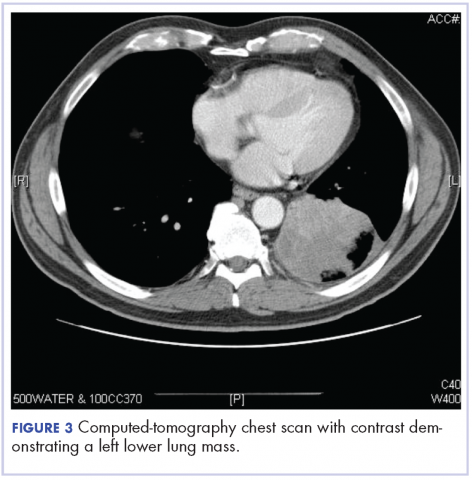

After the diagnosis, a chest X-ray showed that the patient had a left lower lung mass. The results of his physical exam were all within normal limits, with the exception of decreased visual acuity in the left eye. The results of his laboratory studies, including complete blood count and serum chemistries, were also within normal limits. Imaging studies – including a computed-tomography (CT) scan of the chest, abdomen, and pelvis and a full-body positron-emission tomography–CT scan – showed a hypermetabolic left lower lobe mass 4.5 cm and right lower paratracheal lymph node metastasis 2 cm with a small focus of increased uptake alone the medial aspect of the left globe (Figures 3 and 4).